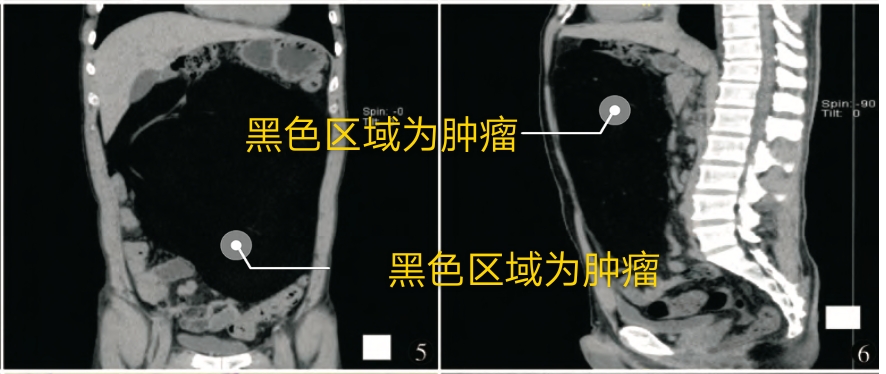

腹腔盆腔可见巨大肿块,占满腹盆腔,病灶呈脂质低密度,其密度不均,增强后无明显强化,肝脏受压,肝门部变形,胰腺受压变形。肿瘤体积约32×22×15cm。考虑为脂肪肉瘤。

冠状位,矢状位观察,肿瘤几乎占满腹盆腔,将肠管挤向边缘